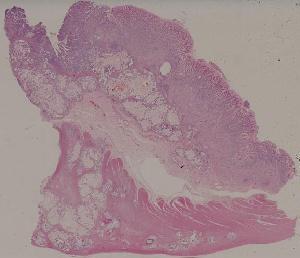

66. Active nodular cirrhosis of the liver